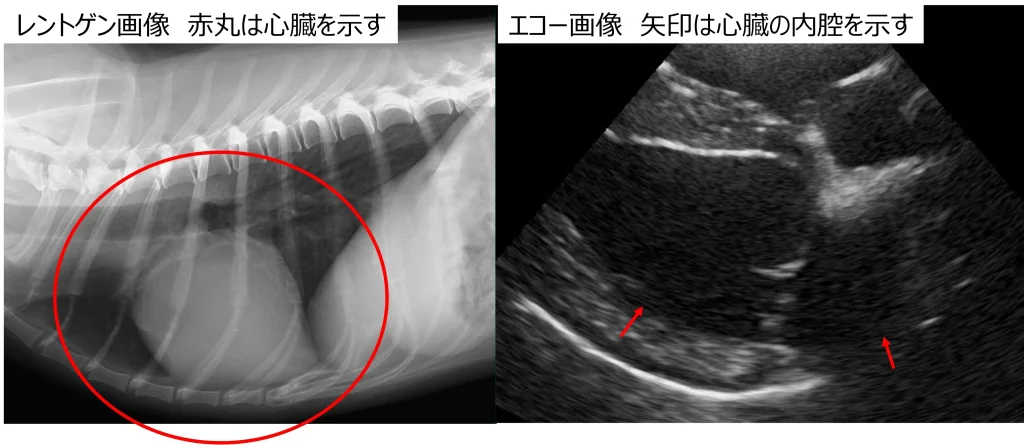

エコー検査では臓器の形や大きさだけではなく、臓器の内部まで見ることが可能です。ただ臓器の一部分を詳細にみることはできますが、臓器全体像が見えにくいという短所もあります。

対してレントゲン検査では撮影の際に予め撮影したい部分の範囲を決めます。そうすることで胸の中であれば心臓・肺・気管・骨など、お腹の中であれば胃・肝臓・脾臓・腎臓・消化管・骨などの画像に写る全ての組織や臓器を見ることが可能です。臓器の形や大きさを見ることはできますが、臓器の内部までは見ることができません。

エコー検査では心臓の動きや血液の流れまで見ることができ、静止画だけではなく動画として評価することができます。レントゲン検査では撮影したものをすぐに評価することは可能ですが、画像は静止画のみで読み取らなければいけません。